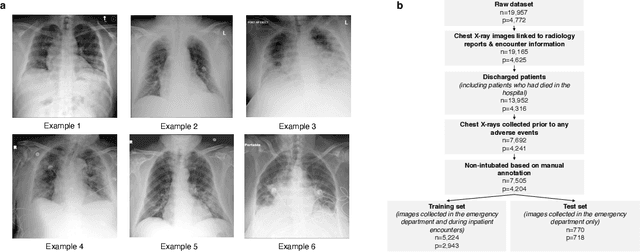

Abstract:During the COVID-19 pandemic, rapid and accurate triage of patients at the emergency department is critical to inform decision-making. We propose a data-driven approach for automatic prediction of deterioration risk using a deep neural network that learns from chest X-ray images, and a gradient boosting model that learns from routine clinical variables. Our AI prognosis system, trained using data from 3,661 patients, achieves an AUC of 0.786 (95% CI: 0.742-0.827) when predicting deterioration within 96 hours. The deep neural network extracts informative areas of chest X-ray images to assist clinicians in interpreting the predictions, and performs comparably to two radiologists in a reader study. In order to verify performance in a real clinical setting, we silently deployed a preliminary version of the deep neural network at NYU Langone Health during the first wave of the pandemic, which produced accurate predictions in real-time. In summary, our findings demonstrate the potential of the proposed system for assisting front-line physicians in the triage of COVID-19 patients.